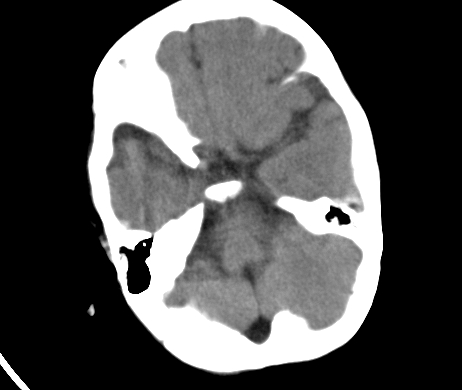

标题: PED1850:男 2岁 头部外伤1天,有事吗?

男 2岁 头部外伤1天,有事吗?科里意见不一 骨窗 没事,未上传

未见与外伤有关病变;脑白质的比例较少,有发育异常吗?